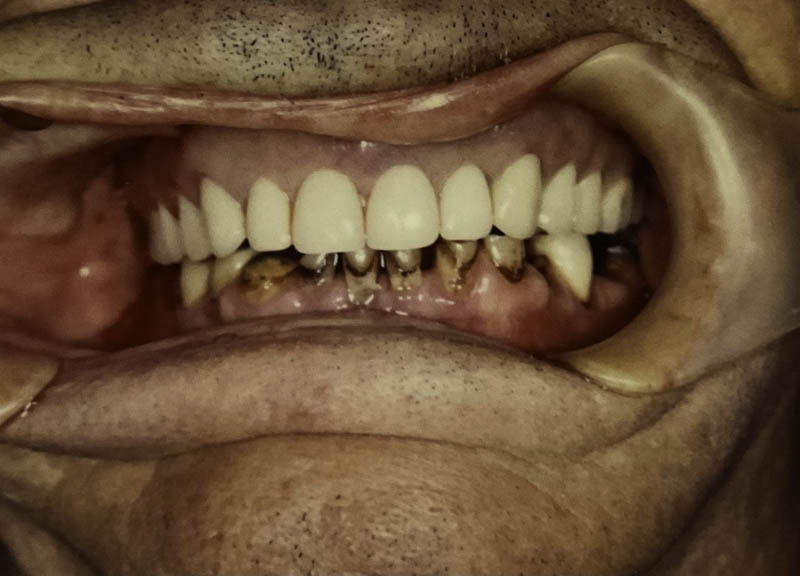

Cosmetic Crowns

Case Highlight

Before

After